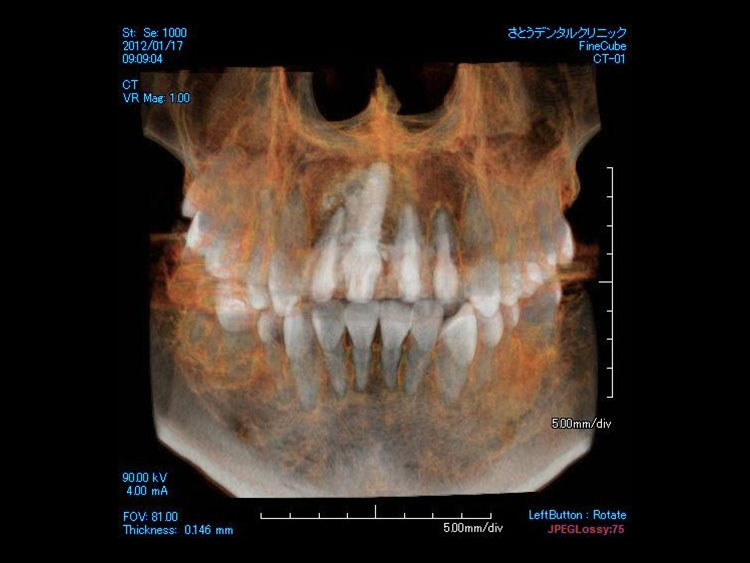

インプラント症例 Case3

Treatment cases

Before

After